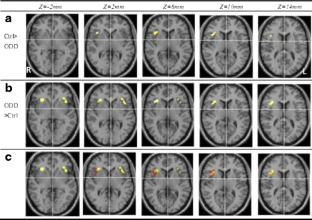

Functional Magnetic Resonance Imaging (fMRI) of inhibitory control has only been investigated in patients with attention deficit hyperactivity disorder (ADHD) and conduct disorder (CD). The objective of this study was to investigate the differences of functional areas associated with inhibitory control between boys with pure oppositional defiant disorder (ODD) and controls during a response inhibition task using functional magnetic resonance imaging (fMRI). Eleven boys with pure ODD and ten control boys, aged 10 to 12, performed a GoStop response inhibition task in this study. The task has a series of “go” trials to establish a pre-potent response tendency and a number of “stop” trials to test subjects’ ability to withhold their responses. During the GoStop task, greater activation in the dorsolateral parts of the bilateral inferior frontal gyrus, left middle frontal gyrus (lMFG) and right superior frontal gyrus (rSFG) activation was seen in the ODD boys. Additionally, reduced activation in regions of the right inferior frontal gyrus (rIFG) was seen in the ODD boys in comparison with the control group. The results may suggest that the higher activation in areas adjacent to the rIFG could be the cause of reduced activation in the rIFG; although this is speculative and requires additional supporting evidence. The findings further suggest that ODD is a less pronounced functional disorder compared to ADHD and CD.

Fig. 1